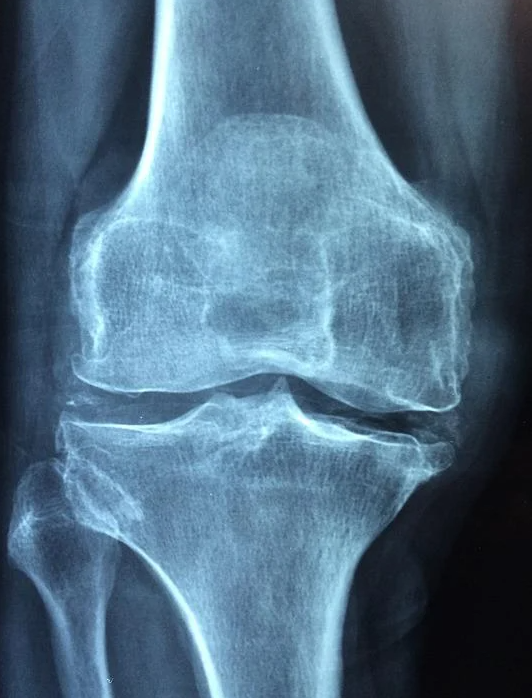

7) 골다공증 원인

수면이 부족하면 골밀도를 낮추고 뼈의 기능을 약화시켜서 골절이 쉽게 될 수 있습니다. 골다공증에도 잠이 부족하면 영향을 미치게 됩니다.